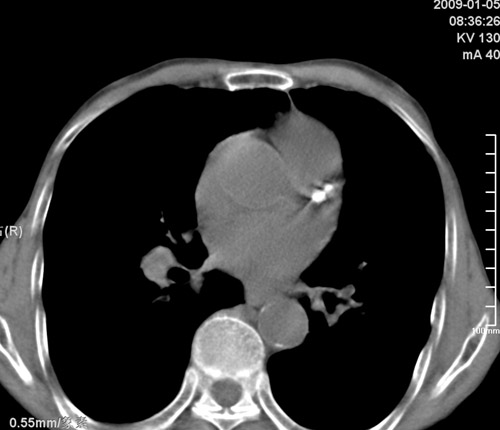

标题: CT17529:男 76 胸背部不适半月 胸透支气管炎 行CT检查 [打印本页]

标题: CT17529:男 76 胸背部不适半月 胸透支气管炎 行CT检查

意见 老年肺 少许炎症 肺大泡 右肺门略大 但支气管通畅  请各位高手指教如何下意见

支持楼主意见,右肺门略大,可能为肺动脉增粗.

慢支肺气肿,肺动脉高压.